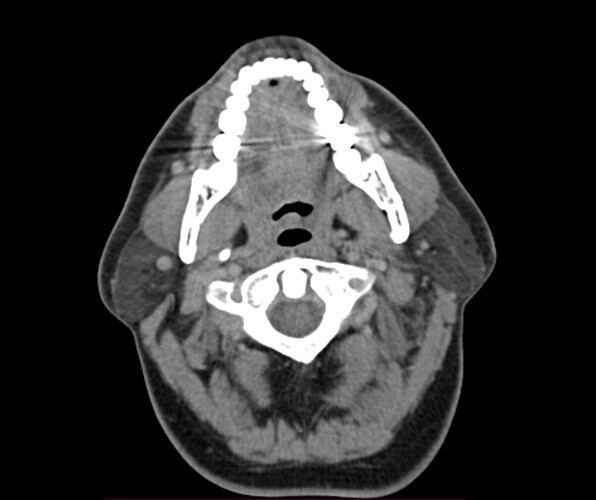

Typically, in the context of vascular ES, the most relevant view is of C1 in the axial view. I’ve attached my own imaging to help you know what to look for. It’s the top vertebrae with a white circle in the top middle:

Hey all thanks, will take a look at the video shortly, in the meantime here’s the axial view, I think.

@jalexy12 see attached annotated imaging.

It’s hard to see, but I believe your your right IJV is wedged between your posterior digastric and C1. The right styloid is not in contact with anything, at least at this level.

Left IJV appears to have some compression against C1. Left styloid is not present at this level.